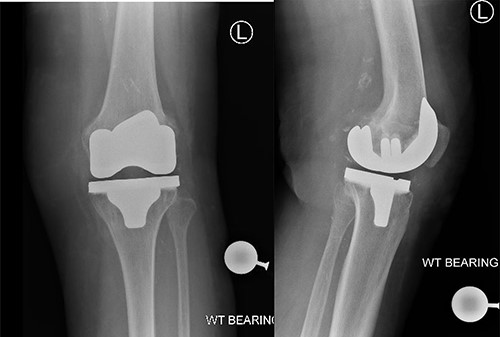

A 83-year-old lady, previous history of breast cancer treated with mastectomy and chemotherapy and in remission was referred to the orthopaedic outpatient clinic by her general practitioner (GP) with a 3-week history of a superficial skin lesion with multiple granulating areas with discharge along the midline scar of a previous total knee replacement, Fig. 1.The primary total knee replacement was done 24 months ago in February 2018, wound healed well with no evidence of infection. The range of motion after the knee replacement was from 0° to 110° of flexion, Fig. 2. She also had recent urinary tract infection (UTI) with pseudomonas and has been on long-term oral antibiotics for recurrent UTI in the past for the last 12 months. Wound swabs from the total knee replacement scar done by GP showed pseudomonas growth.

Post-operative radiographs showing satisfactory position of prosthesis for left total Knee replacement.